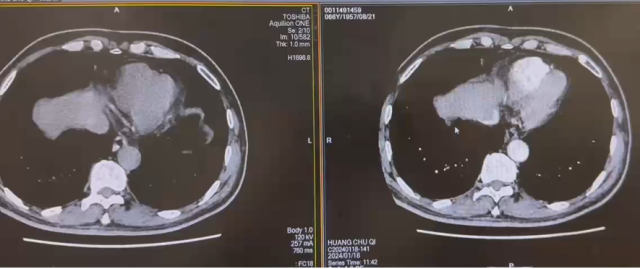

新辅助治疗前

新辅助治疗后

治疗后复查 CT(2022.7):左肾透明细胞 CA 治疗后改变,肿块较前缩小,强化程度减低,左侧副肾动脉可见;余况同前。

CT(2022.1):1. 左肾肿块,肾癌并出血可能;2. 左输尿管上段结石并周围炎症,左肾结石并积水;3. 右肾萎缩;4. 肝囊肿。